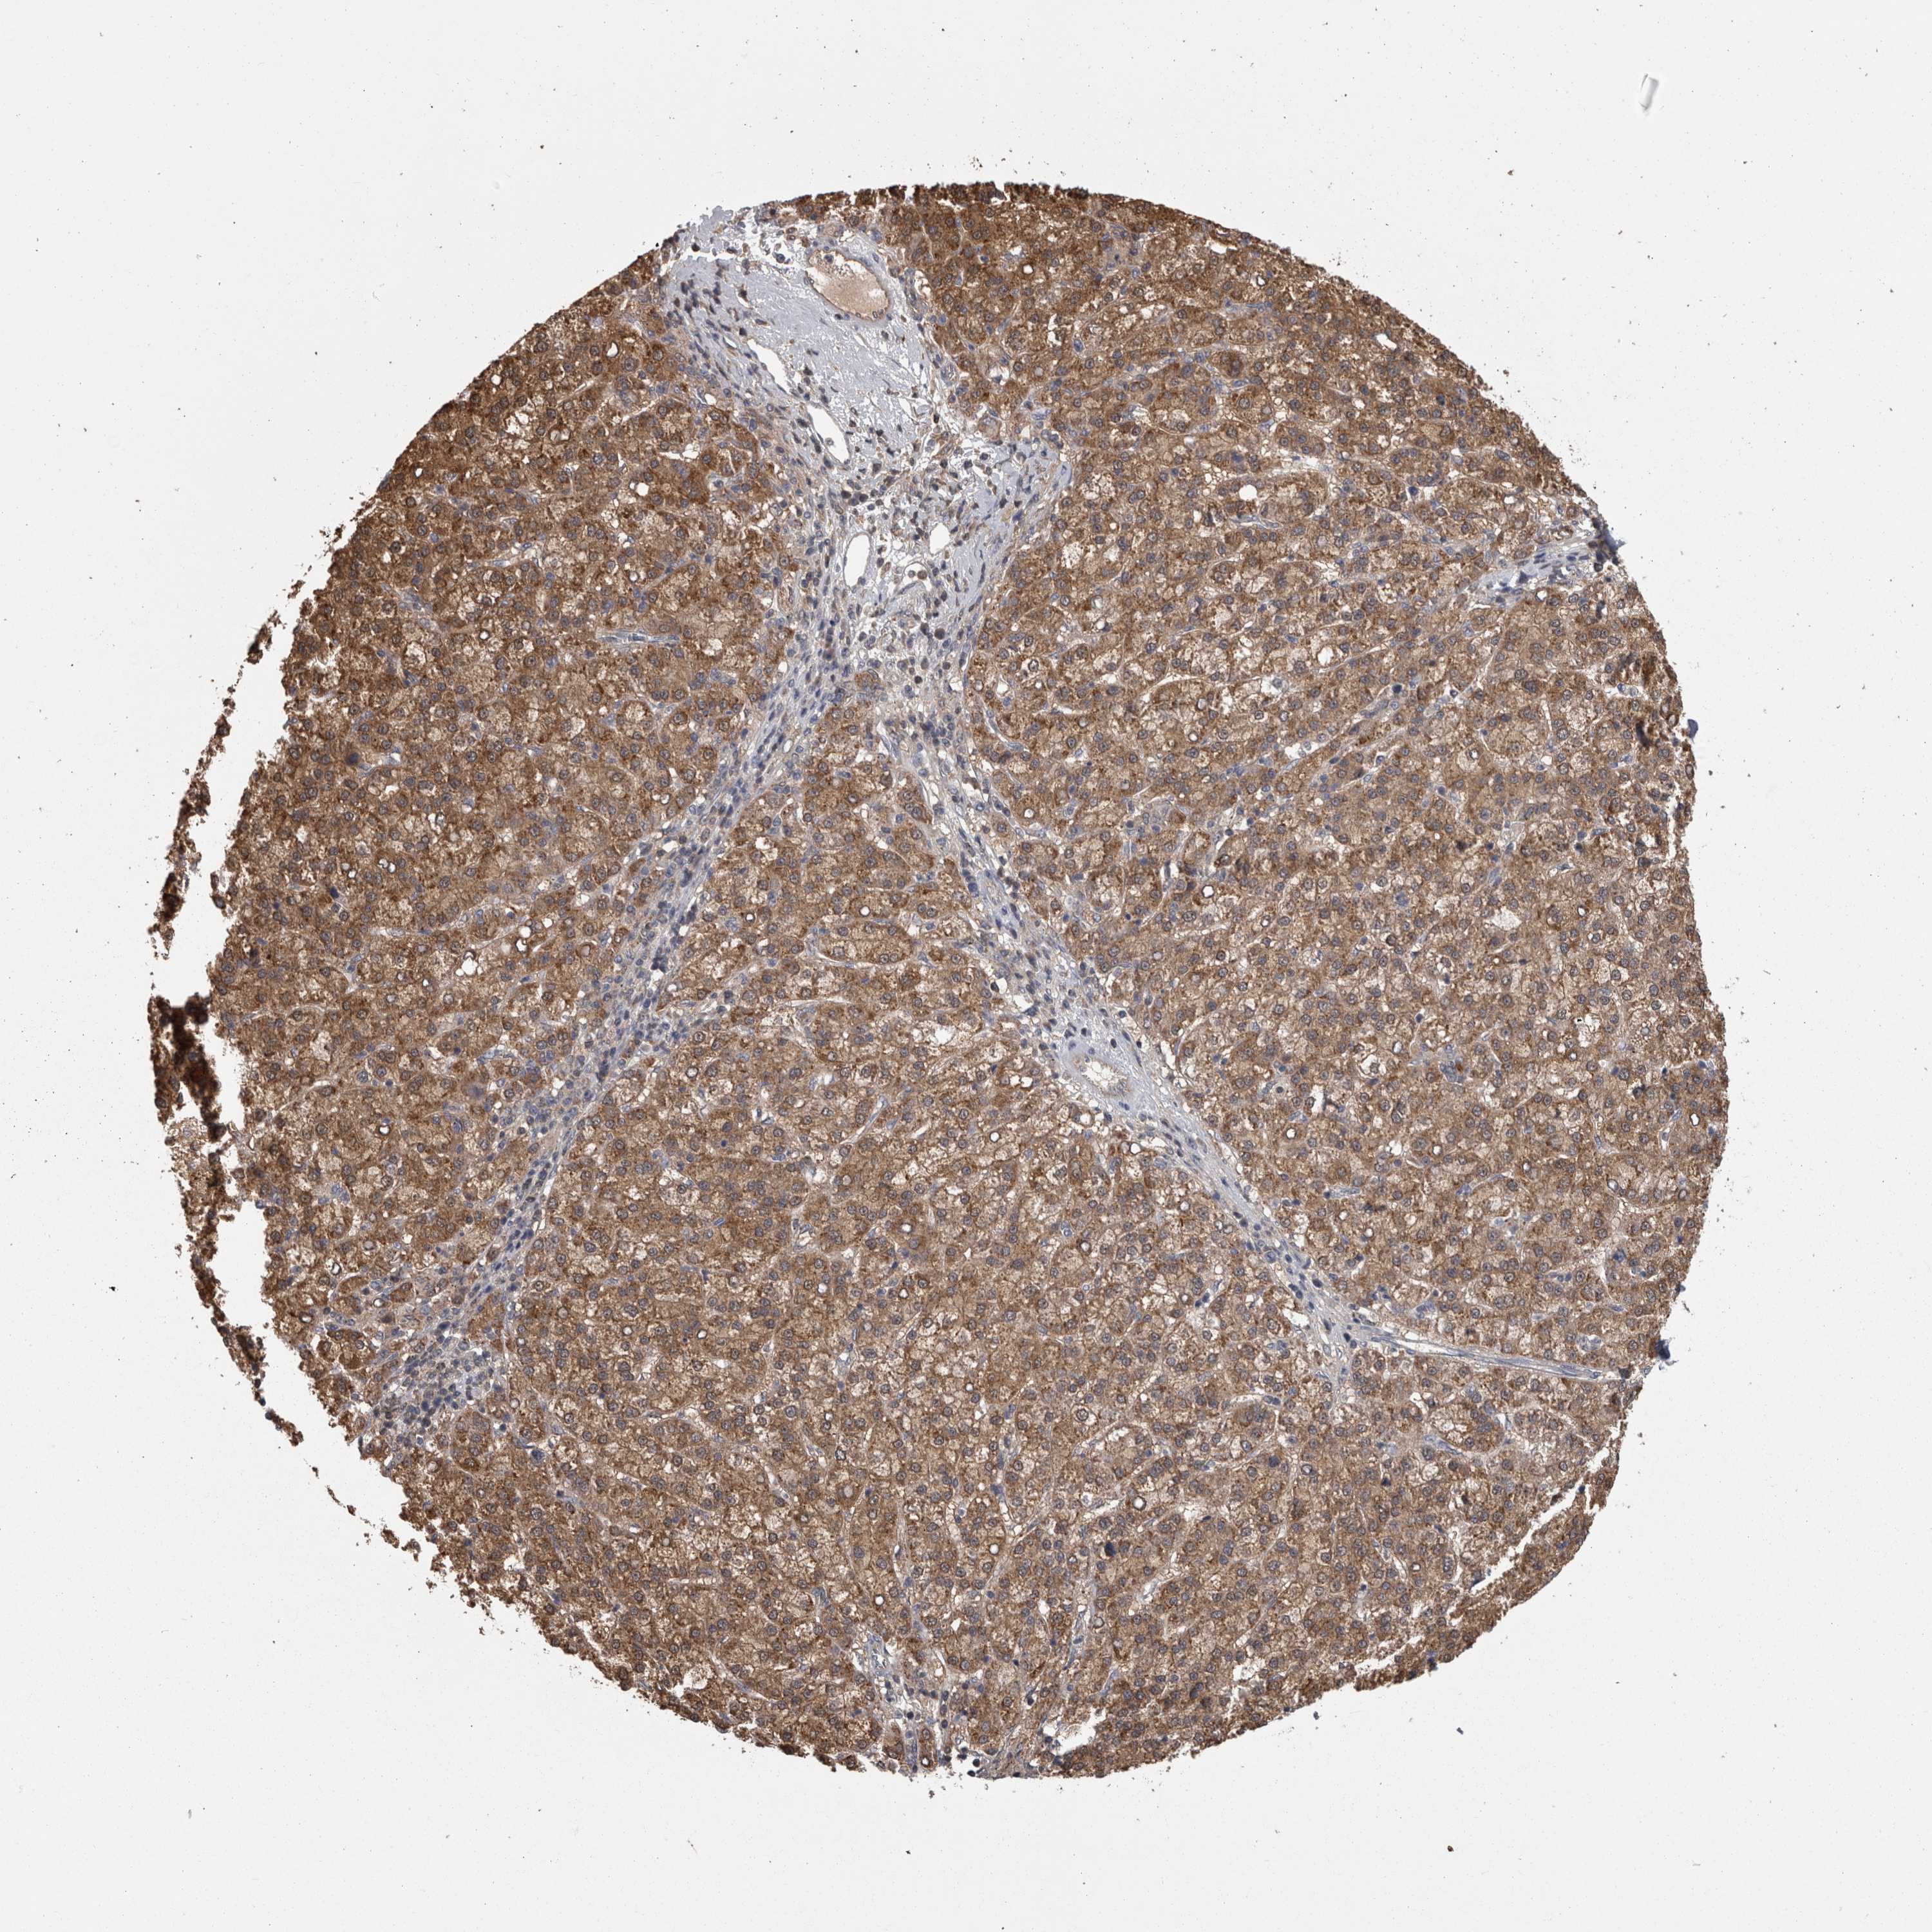

LIVER CANCER - Protein expressioni

A mouse-over function shows sample information and annotation data. Click on an image to view it in a full screen mode. Samples can be filtered based on level of antibody staining by selecting one or several of the following categories: high, medium, low and not detected. The assay and annotation is described here.

Note that samples used for immunohistochemistry by the Human Protein Atlas do not correspond to samples in the TCGA dataset.

Antibody stainingi

Antibody staining in the annotated cell types in the current human tissue is reported as not detected, low, medium, or high, based on conventional immunohistochemistry profiling in selected tissues. This score is based on the combination of the staining intensity and fraction of stained cells.

Each image is clickable and will lead to virtual microscopy that enables deeper exploration of all samples and also displays staining intensity scores, fraction scores and subcellular localization as well as patient and tissue information for each sample.

Antibody HPA026681

Staining

High

Medium

Low

Not detected

Intensity

Strong

Moderate

Weak

Negative

Quantity

>75%

75%-25%

<25%

None

Location

Nuclear

Cytoplasmic/membranous

Cytoplasmic/membranous,nuclear

Cholangiocarcinoma

Carcinoma, Hepatocellular, NOS